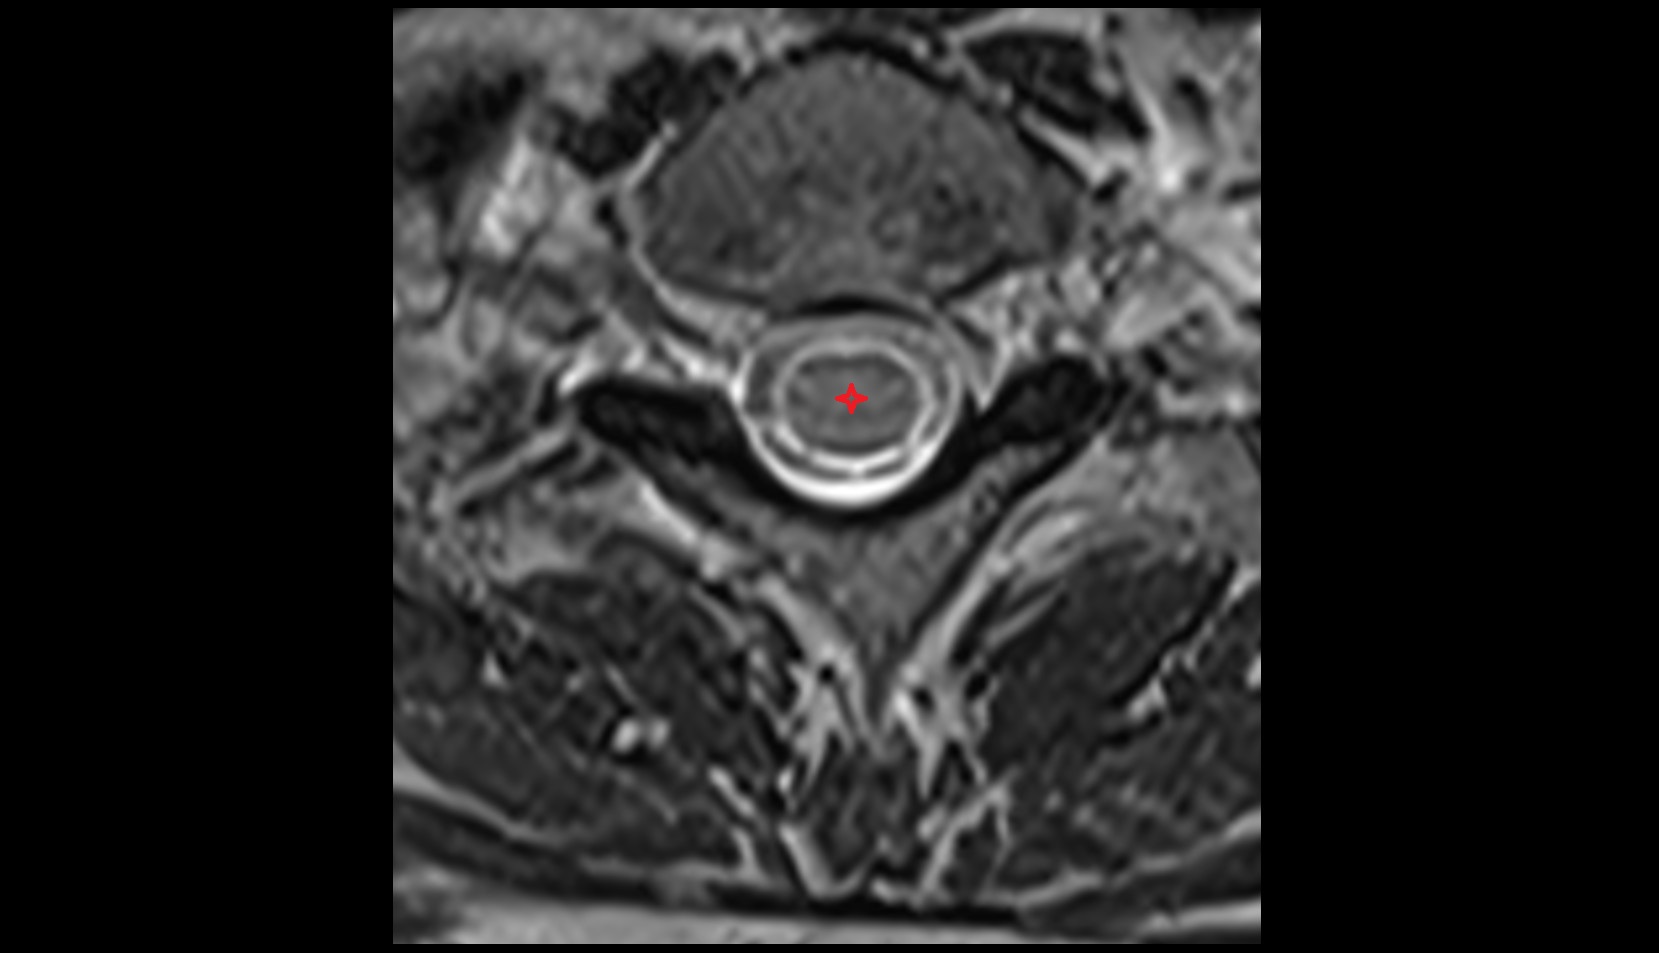

- Spinal cord

- subarachnoid space of spinal cord